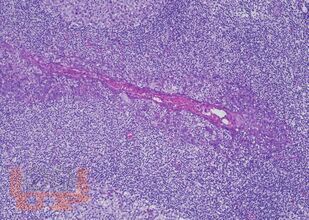

Настоящее руководство-атлас посвящено патоморфологической диагностике опухолей полости носа и носоглотки. Несомненным достоинством книги является систематизированное, лаконичное и вместе с тем весьма информативное изложение текстового материала (клинико-эпидемиологическая картина, морфологическая характеристика, дифференциально-диагностический ряд, необходимые дополнительные методы исследования), а также более 170 цветных микрофотографий наблюдений из собственной клинической практики с подробными подписями. Наряду с опухолями в книге представлен раздел наиболее часто встречающихся неопухолевых процессов синоназального тракта, необходимых для дифференциального диагноза.

Руководство-атлас предлагает структурированный подход с унифицированным изложением современных данных о клинических и морфологических особенностях доброкачественных и злокачественных опухолей носа и носоглотки.